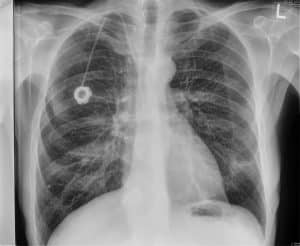

The case below showcases a traditional DR and two dual-energy X-ray images taken in a single exposure by Reveal 35C in PA view. While this example uses a PA view, Reveal 35C supports all imaging views — including lateral and oblique. From left to right: traditional DR, soft tissue, and bone image.

PA X-ray image taken by single-exposure dual-energy X-ray system Reveal 35C

PA soft tissue image taken by single-exposure dual-energy X-ray system Reveal 35C